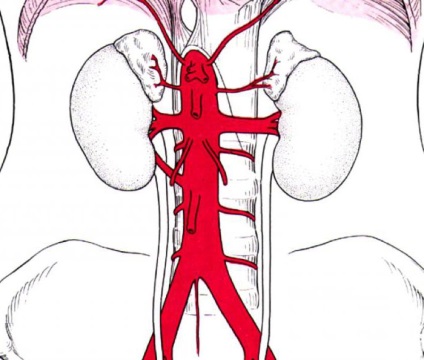

hasi aorta ágak

Hasi szegmensben az aorta - folytatása mellét része. Úgy kezdődik a szint hátcsigolya 12, áthalad az aorta rekeszi nyitó és végződik a régióban a 4 ágyéki csigolya.

parietális ágak

Osztja következő parietális ága a hasi aorta:

- Rekeszsérv alsó artéria (jobb és bal) ágaznak ki a hasi aorta után kilép a aorta nyíláson és rekeszizom kövesse a membránt (az alsó sík) előre és felfelé és kb.

- Lumbális artériák (4 db) kiindulva az aorta a régióban a felső ágyéki csigolya 4, ellátási vért a anterolaterális felülete a gyomor, gerincvelő, és a hát alsó részén.

- Középső keresztcsonti artériát eltér az aorta tartományában annak felosztását a közös csípő artériák (5 ágyéki csigolya) követi a kismedencei részét a keresztcsont, krovosnabzhaya farkcsontot, keresztcsont és m. iliopsoas.

zsigeri ágai

Osztja következő zsigeri ágai a hasi aorta:

- Celiac trunk származik az aorta körüli 12 háti vagy lumbális csigolyák 1, rekeszsérv a belső lábak. Az előrejelzések a középvonalon le a kardnyúlvány (felső). A területen a test a hasnyálmirigy lisztérzékenység csomagtér, ami három ága van: a bal gyomor-, máj- és lépartéria gyakori. Truncus coeliacus körül napfonat ágak és fedett az első a parietális hashártya.

- A mellékvese artéria átlagos gőz, ágazik el az aorta alatt a coeliakia törzs és ellátja a mellékvesében.

- Felső mesenterialis artéria ágazik le az aorta a régióban az 1. ágyéki csigolya, posterior a hasnyálmirigy. Ezután áthalad a nyombél (elülső felület) és elküldi ágak a duodenum és a hasnyálmirigy, alábbi gyökér lemezek között mesenterialis vékonybél, ad egy vékony gallyak a perfúziós és a vastagbélben (jobb oldalon) a beleket.

- Veseartériákon származnak 1. ágyéki csigolya. Ezek artériák ad okot alacsonyabb mellékvese artériákban.

- Petefészek-artérián (herék) kiterjesztése alatt a renális artériák. Átadás posterior a parietális peritoneum, át a húgyvezetékek, és miután a külső csípő artéria. Azoknál a nőknél, petefészek-artérián keresztül, az ínszalag, amely felfüggeszti a petefészek, kerülnek a petevezeték és petefészek, és a férfiak - a része a spermavezeték kötélen az inguinalis csatorna megy a herék.

- Artéria inferior mesenterialis ágak alsó harmadában a hasi aorta a régióban a 3 ágyéki csigolya. Ez artéria látja a vastagbél (a bal oldali rész).